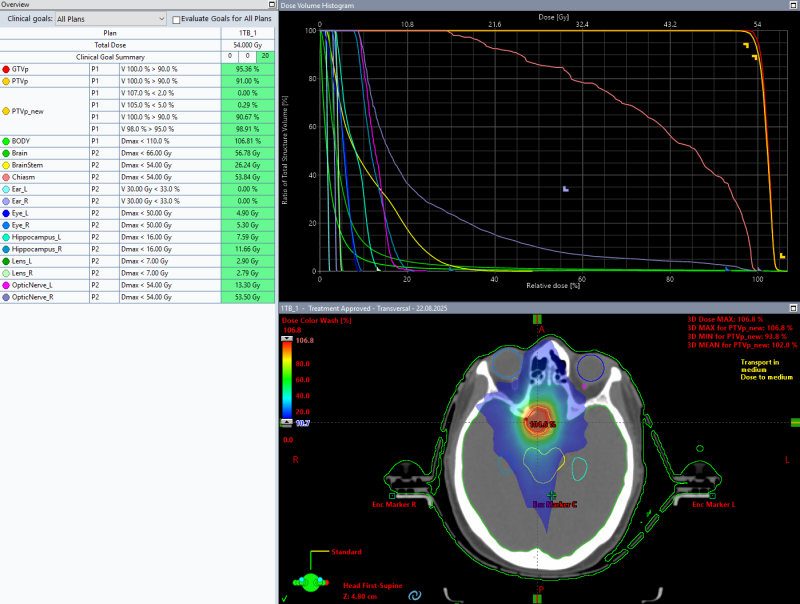

Благодаря использованию современного оборудования — линейного ускорителя Varian TrueBeam — и грамотному оконтуриванию мишени облучения, нам удалось разработать индивидуальный план лучевой терапии. Для обеспечения высокой точности лечения применяется жесткая фиксация специальными термопластическими масками, которые изготавливаются индивидуально под каждого пациента. Это позволяет исключить любые смещения во время процедуры. Лечение является безболезненным для пациента, что значительно повышает комфорт и качество проведения процедуры. Точное планирование позволяет минимизировать воздействие на окружающие органы риска, сохраняя функцию зрения. Ежедневный контроль положения мишени с помощью высокоточной системы навигации обеспечивает доставку дозы точно в цель, что повышает эффективность и безопасность процедуры.